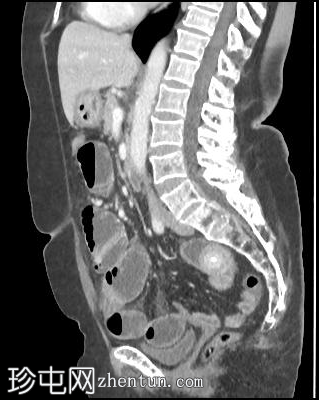

轴位增强扫描(门静脉期)

胆囊缩小,囊壁增厚,提示慢性炎症改变。胆囊(底部)与十二指肠(球部)腔之间可见细小瘘管,胆囊内及肝内、肝外胆管内均可见气体(胆道积气)。

远端空肠内嵌顿一枚较大的胆结石(3.5 cm),近端空肠袢扩张,回肠袢、末端回肠及结肠均塌陷。